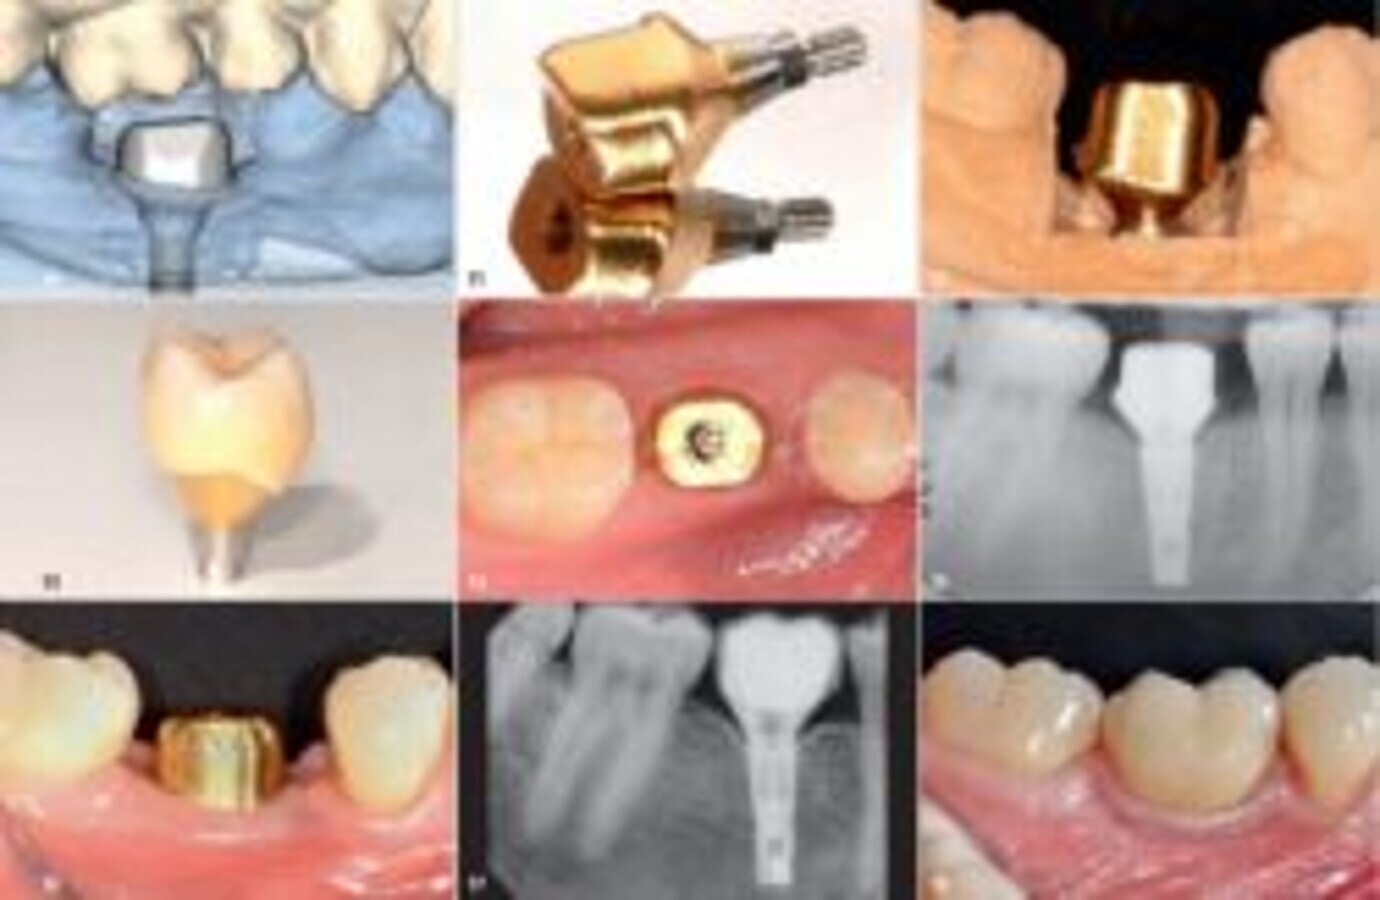

图10:根据被替换磨牙的实际露出宽度设计Atlantis基台,用钛制造,外层涂有氮化钛涂层。

图11:Atlantis镀金钛合金基台和配套螺丝钉一起被送往牙科实验室。

图12:基台的龈下部分将为周围软组织提供解剖外形、支持和色泽。最后的修复冠由氧化锆制作。

图13:最终种植修复的修整线应接近牙龈边缘,以便于去除龈下区域多余的水门汀。修复体已准备好交给病人。

图14:Atlantis基台置于软组织上并稍加压,几分钟后缺血恢复,基台正确就位。

图15:使用X线机器检验基台是否正确就位。注意基台的过渡部分应遵循骨轮廓。

图16:根据制造商建议,将镀金钛合金Atlantis基台以25Ncm扭矩拧紧。螺丝钉头被覆盖,之后牙冠用水门汀粘于基台上。

图17:十年后X线显示修复体、为邻面乳头创造的空间和种植体水平的骨量非常合适。

图18:十年后观察到修复体周围软组织适应良好(颊面视图),邻面乳头填充了预留空间,形成自然的软组织轮廓。